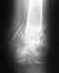

Стоит ли делать операцию? при переломе 5 плюсневой кости со смещением расхождение 0.4 см (снимок прилагается)

Добрый вечер, Случилось следующее: подруга в боулинге подвернула ногу, сначала думали ушиб и в травму не обращались. По пришествию недели опухоль не спадала обратились к врачу, послали на рентген выяснилось что перелом 5 плюсневой кости. Наложили гипс сказали придти через неделю сделать контрольный снимок. сегодня сделали снимок на нем видно смещение 0.4 см. Хирург в больнице сказал что нужно оперировать и ставить пластину, и сказал проконсультироваться хирургом в поликлинике, на что она(хирург поликлиники) сказала что надо проконсультироваться с хирургом в больнице. причем оба не дают уверенного ответа нужна или не нужна операция.